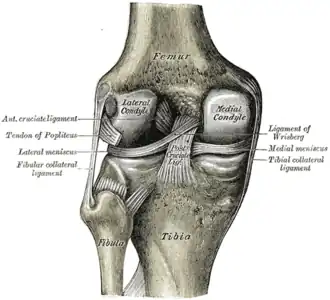

Left knee-joint from behind, showing interior ligaments. (Lateral meniscus and medial meniscus are cartilage.) | |